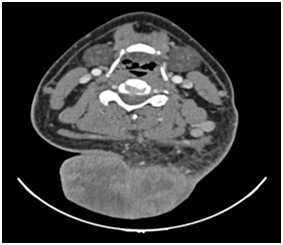

No discarded tumor activity suggested in lung nodule surveillance (Figure 3). Surgical resection of primary lesion dimensional oncologic margins and partial thickness graft of skin. Cervical treatment was delayed until recovery program (Figure 4) (Figure 5); HPR: high-grade mucoepidermoid carcinoma with vascular lymphatic permeation and extensive areas of necrosis and perineural invasion. Tumor size: 14x10x9cm-free surgical margins of neoplasia; the closest to 2cm, 2.6cm surgical bed to the IHC neoplasia: PAS with and without diastase alcian blue and mucicarmine: Positive for mucin (+++), cytokeratin 7, cytokeratin 8 p.63. Epithelial Membrane antigen: Positive focal (++), cytokeratin 14, cytokeratin 20. TTF -1: Negative (-) (Figure 6) (Figure 7).

Figure 3 CT Scan, Tumor in the right posterior cervical neck region> 10 cm and tumor mass 14x10x9cms with thrombosis of right internal jugular vein.